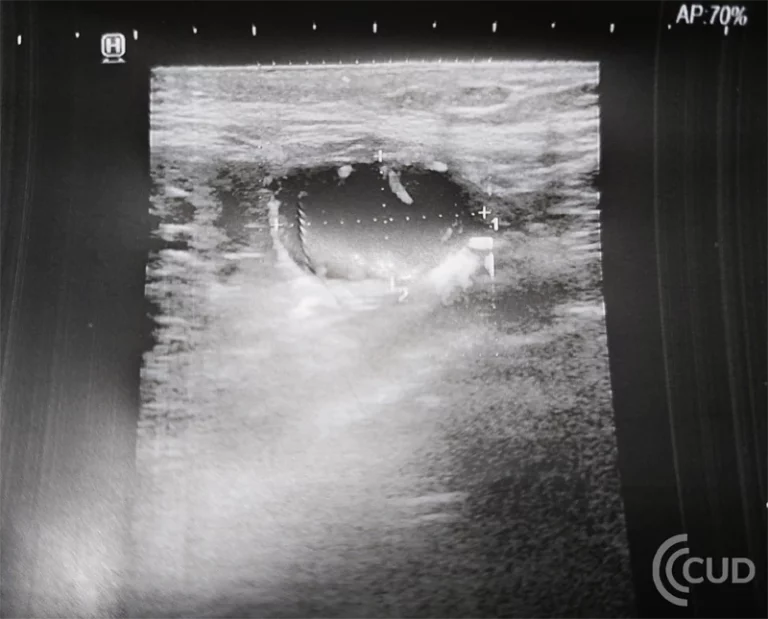

Do gabinetu USG zgłosiła się pacjentka z powodu sporadycznie występującego krwinkomoczu bez innych dolegliwości bólowych. W wykonanym badaniu USG jamy …